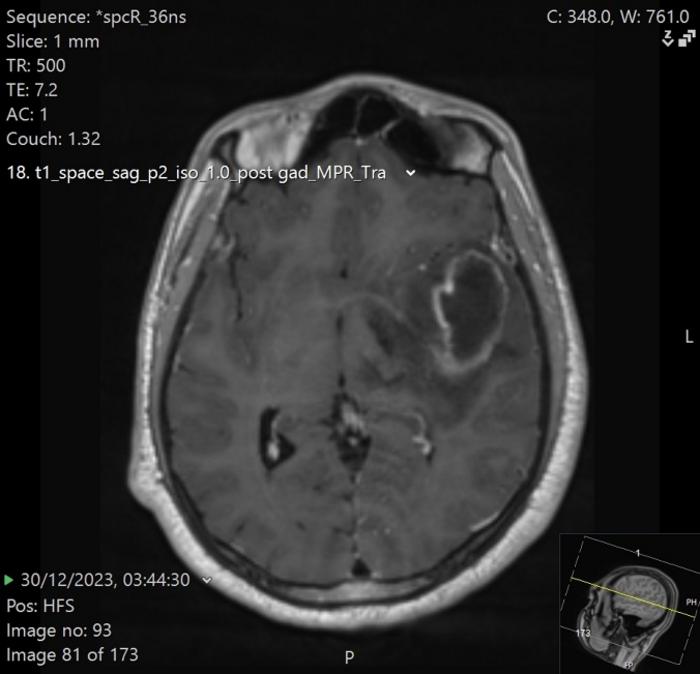

image: MRI image of left temporal brain abscess.

In a recent case, doctors in a UK emergency department used a portable transcranial ultrasound (TCUS) machine on a 33-year-old man with a worsening headache. The scan, performed through the temporal bone window, revealed a suspicious dark (hypoechoic) area in the brain with bright (hyperechoic) walls. This finding, while not conclusive, promptly triggered an urgent MRI that confirmed a brain abscess, and the patient was rushed to successful neurosurgery.